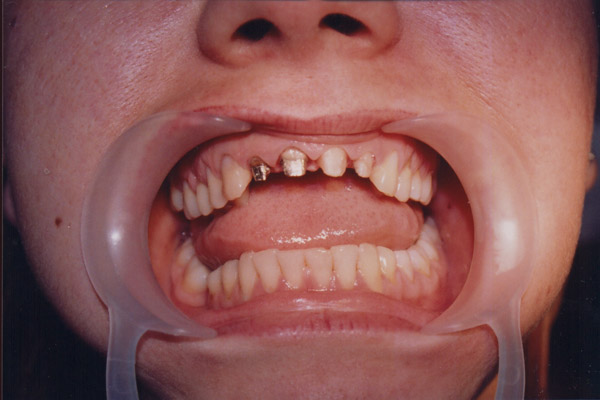

"Je suis très content des soins qui m'ont été prodigués par le Dr Manu et je ne peux que vous le conseiller fortement. Moi j'ai pay pour chaque implant 550 Euros et 190 Euros par couronne du porcelaine sur métal qui on été fait par des prothésistes qui sont à 2mn en voiture du cabinet du centre ville (Il en a deux et selon les soins vous allez à l'un ou à l'autre) et souvent il m'a prodigué des soins gracieusement. En france ou autour on aurait multiplié la facture par 2 au moins."